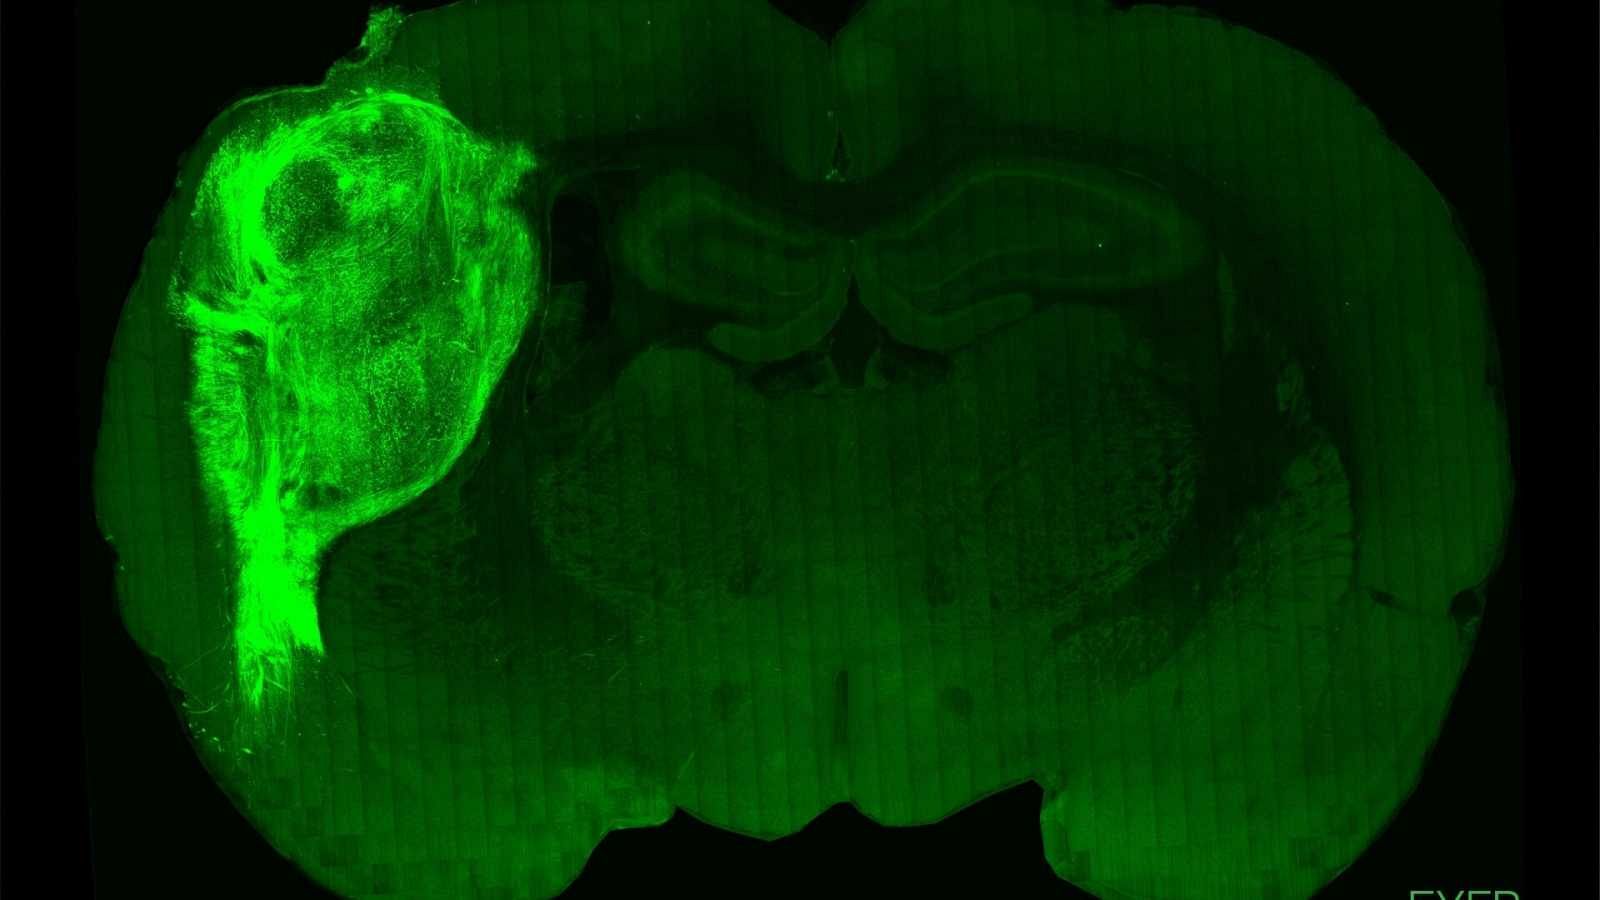

Implantan 'minicerebros' humanos en ratas recién nacidas y logran influir en su comportamiento

Un equipo de científicos de la Universidad de Stanford en EEUU ha conseguido trasplantar neuronas humanas al cerebro de ratas recién nacidas y...